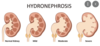

What is hydronephrosis?

- kidneys become stretched and swollen as the result of a build-up of urine inside them